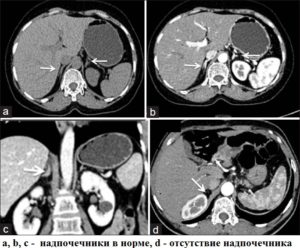

На КТ и МРТ видны образования и другие патологии на обоих надпочечниках.

Магнитно-резонансное исследование покажет изменения, связанные с органами. Надпочечники должны иметь однородную структуру, четкие границы, линейную и треугольную форму. Толщиной орган не должен превышать 10 мм, а ножки пять мм. При наличии опухолей их можно легко заметить на снимках.

Компьютерная томография эндокринных желез позволяет определить их расположение, оценить форму и установить плотность тканей. На фоне четкого изображения железы круглыми или овальными областями выделяется аденома надпочечника. Данная патология выявляется на КТ с 98% точностью.

А – аденома (стрелка) правого надпочечника; Б – синдром Кушинга, кортикостерома правого надпочечника.

Гиперплазия надпочечников, которая также хорошо диагностируется томографией, характеризуется на снимках заметным увеличением объема желез. Форма органов при этом не отклоняется от нормы. Патология развивается в коре надпочечников и достаточно трудно диагностируется традиционными методами обследования.